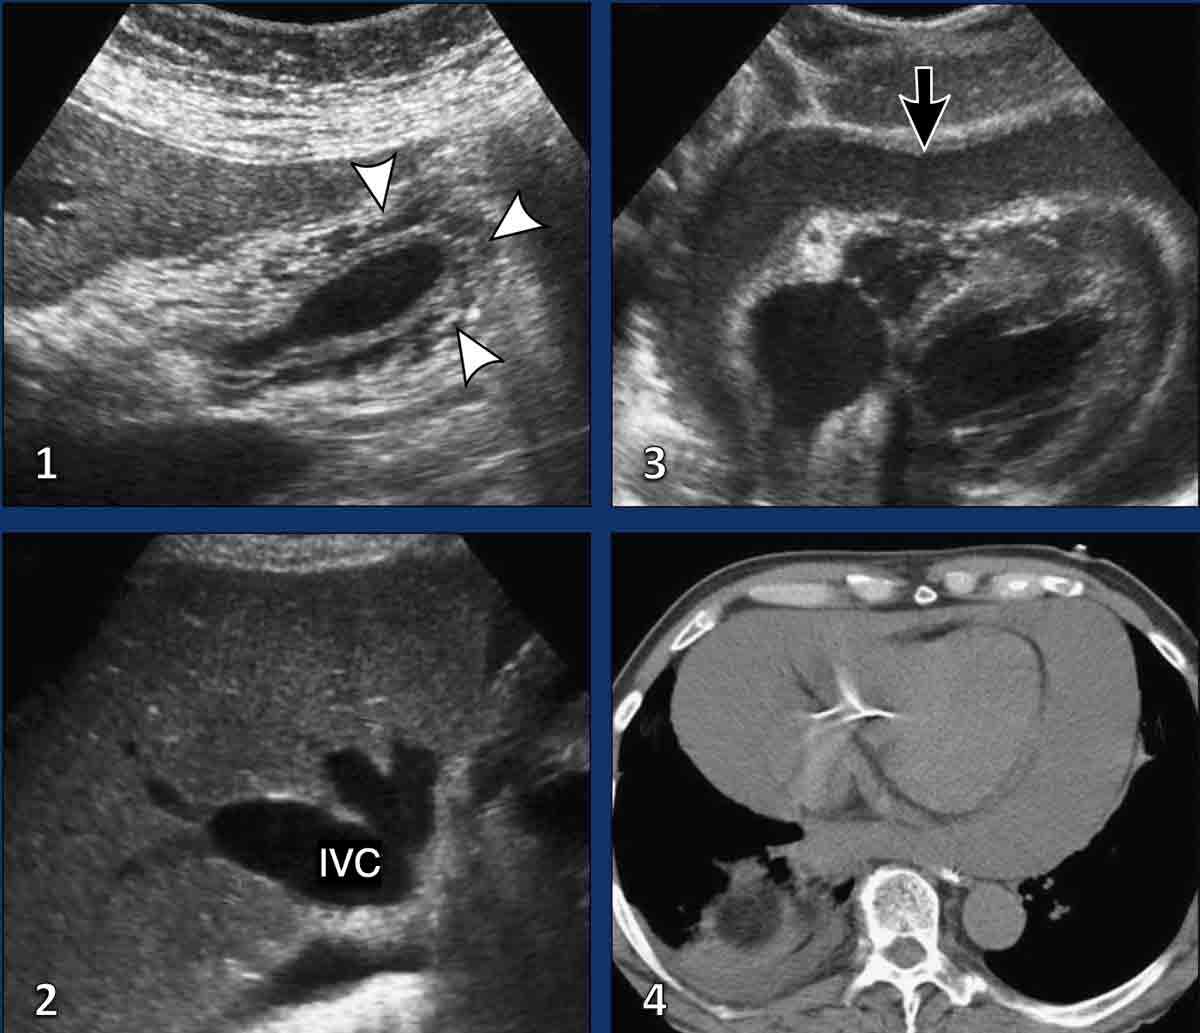

Các hình ảnh này thuộc về một phụ nữ 53 tuổi bị thuyên tắc phổi cấp tính, biểu hiện với các dấu hiệu lâm sàng của viêm túi mật.

Hình ảnh

Siêu âm qua gan cho thấy dịch màng phổi một bên (đầu mũi tên). Túi mật bình thường (không hiển thị). Trong quá trình siêu âm, bệnh nhân tiết lộ rằng các triệu chứng khởi phát ngay sau một chuyến bay liên lục địa.

Siêu âm ép phát hiện huyết khối trong tĩnh mạch đùi trái (mũi tên).

CT được thực hiện và phát hiện huyết khối trong động mạch thùy dưới phổi phải và tràn dịch màng phổi lượng ít.

Siêu âm và CT bụng đều có thể xác định các dấu hiệu gián tiếp của thuyên tắc phổi, chẳng hạn như tràn dịch màng phổi một bên, xảy ra trong khoảng 50% các trường hợp. Trong quá trình siêu âm, có thể khai thác tiền sử bệnh có định hướng, và nếu nghi ngờ thuyên tắc phổi, đánh giá có thể được mở rộng kịp thời để bao gồm siêu âm ép tĩnh mạch sâu chi dưới. Điều này có ý nghĩa lâm sàng quan trọng, vì thuyên tắc phổi và huyết khối tĩnh mạch sâu đại diện cho các biểu hiện khác nhau của cùng một phổ bệnh lý huyết khối tắc mạch.

Trình bày ca bệnh

Các hình ảnh sau đây liên quan đến một nam giới 81 tuổi bị thuyên tắc phổi cấp tính, ban đầu biểu hiện với các đặc điểm lâm sàng bắt chước viêm túi thừa đại tràng sigma.

Kết quả hình ảnh

- Siêu âm, sử dụng lách làm cửa sổ âm học, cho thấy đông đặc phổi kín đáo hoặc dịch màng phổi (đầu mũi tên), không phát hiện bất thường ổ bụng.

- Siêu âm phát hiện huyết khối (mũi tên) trong tĩnh mạch khoeo trái.

- Hình ảnh CT tái tạo MIP (hình chiếu cường độ tối đa) mặt phẳng coronal cho thấy huyết khối trong động mạch phổi thùy dưới trái (mũi tên vàng) và nhồi máu phổi (đầu mũi tên), tương ứng với hình ảnh đông đặc quan sát được trên siêu âm.

CT bụng có thể phát hiện, nếu thời gian trễ chụp cho phép ngấm thuốc tương phản tĩnh mạch đầy đủ, huyết khối trong tĩnh mạch chậu hoặc tĩnh mạch chủ dưới (hình).